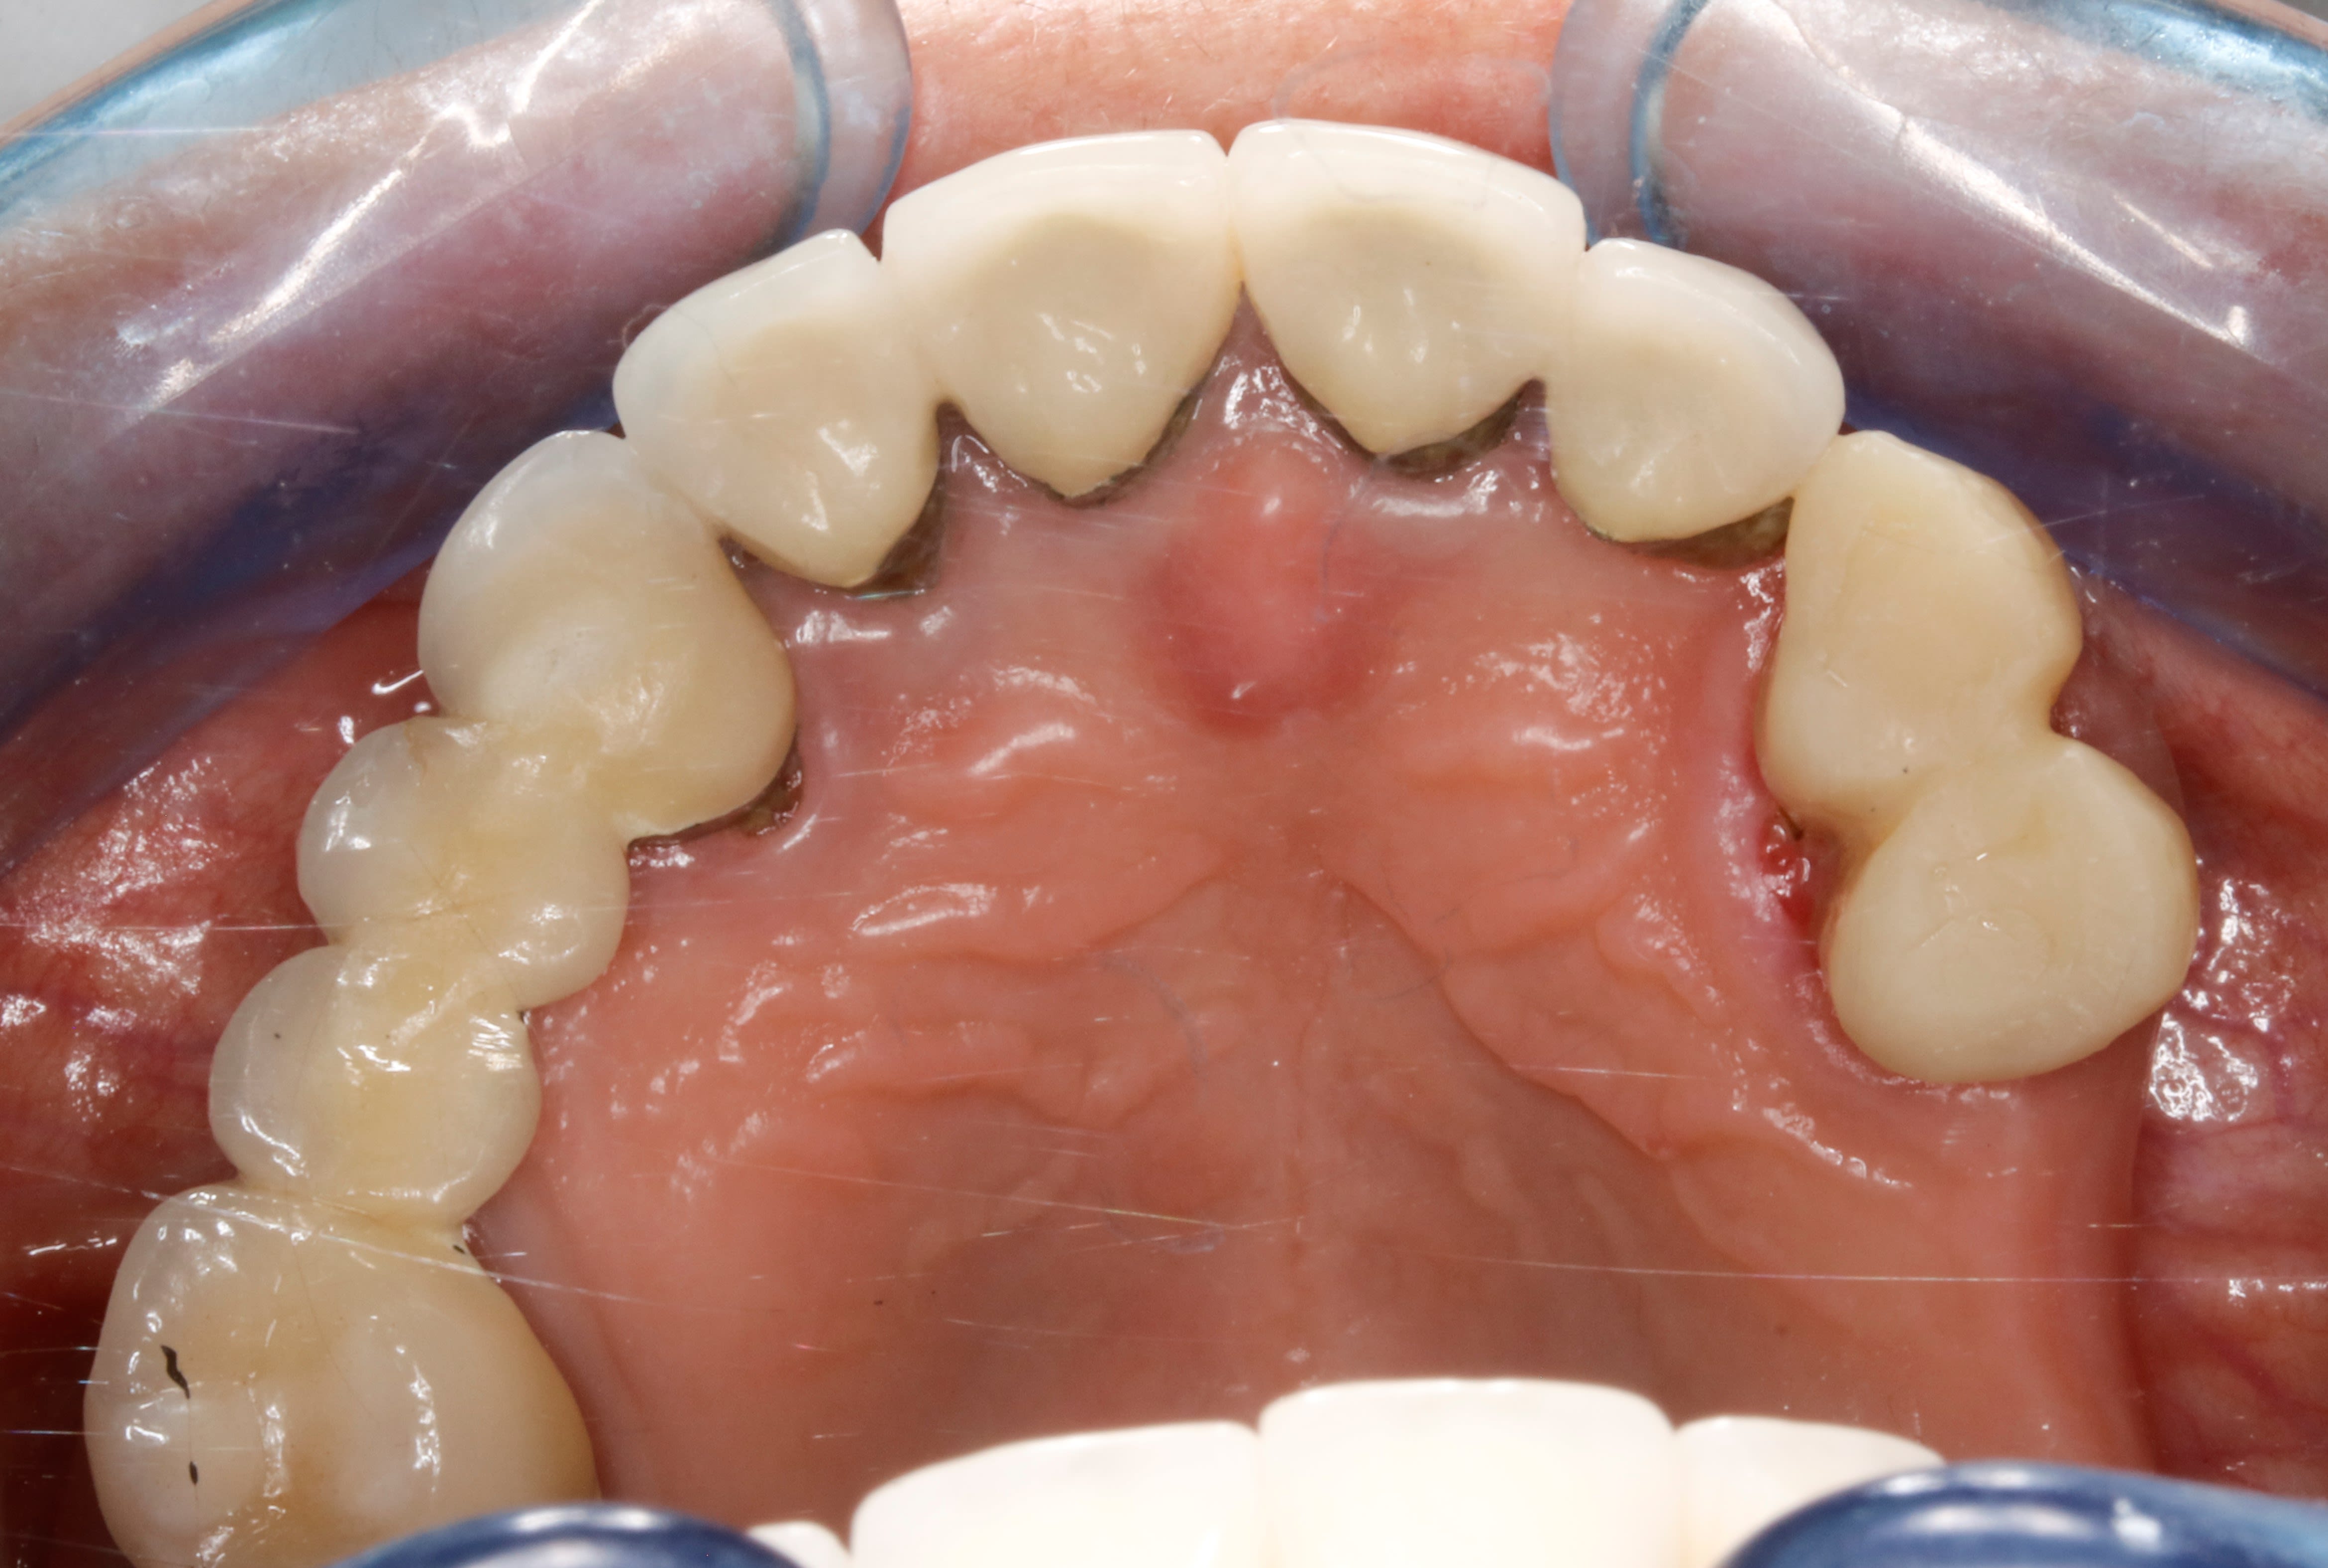

incroyable on parle de vieillerie , et voilà que je viens de recevoir un aure cas que j avais fait et ça tombe bien pcq à elle bien justement je ne lui avais pas fait de ppa .

elle a perdu sa racine de 12 , décidément , et je viens de faire 2 prov sur 13 et 14 qu avaient morflé grave .

au depart quand j avais fait ce boulot le point de depart etait aussi moisi que celui précédemment . c était une méchante classe2 avec béance ( de souvenir ) .

on constatera qu il n y a pas de faces d usures comme sur le premier cas . pourquoi ? bin pcq il n y a pas eu de ppa .

là c est clair aussi .

alors , d apres vous , ça a quel age ce boulot ?? :-))

1993 .